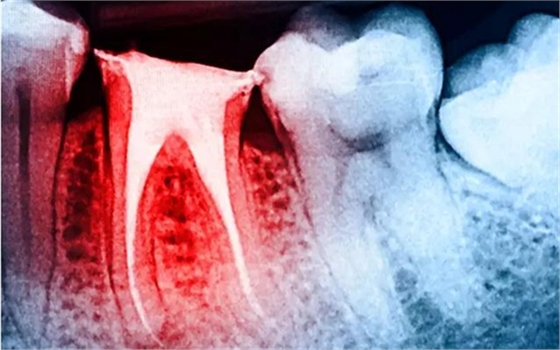

大量研究表明:與活髓牙相比,根管治療后牙體組織的強度、韌性以及硬度等力學(xué)性能均無明顯改變,牙髓活力對牙齒的生物力學(xué)性能的影響十分有限;而齲損組織、舊充填物和后續(xù)的治療修復(fù)過程造成的冠根部牙體組織的喪失才是引起牙齒抗折強度降低的主要原因。牙體強度與剩余牙體組織的量密切相關(guān),牙體組織缺損愈多,抗折力降低愈明顯。